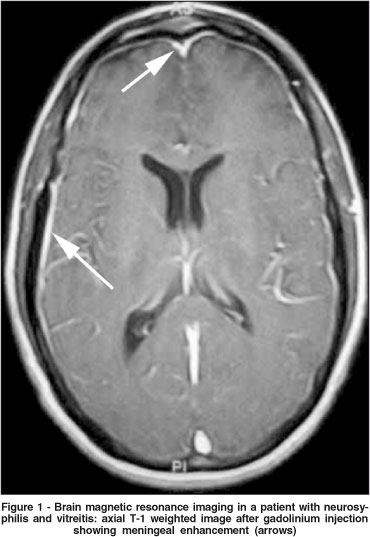

Rapid plasmin reagin - RPR (titer 1:1024) and fluorescent treponemal antibody absorption - FTA-ABS (4+ reactive) were both abnormal. Brain magnetic resonance imaging was significant for meningeal enhancement without focal abnormalities (Figure 1). Cerebral spinal fluid analysis was abnormal: 35 WBCs (100% lymphocytes), protein 57mg/ml, glucose 55mg/ml and positive VDRL (titer 1:4). Additionally, Huntington cytosine-adenosine-guanine (CAG) repeat genetic testing was normal and HIV testing was positive with a CD4 count of 242. Following treatment with intravenous penicillin, a prompt improvement of the vitreitis and chorea was observed.